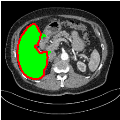

Cross-Domain Generalization:

To test the generalizability of SAM-Mix, we validate it on a cross-domain dataset (TotalSegmentator). As reported in Table 2, the segmentation performance of SAM-Mix on the cross-domain task is as promising as the in-domain results. Despite the data shifts, from LiTS to TotalSegmentator, SAM-Mix outperforms all of the baseline models in terms of generalizability, by significant margins. SAM-Mix-50 achieves a Dice score improvement of 25.4%, and a lower Hausdorff distance by 62.26% compared to the best-performing full-supervised U-Net model. These results further validate the few-shot capabilities and establish our SAM-Mix as a well-generalized tool for medical image segmentation.

![]() |

| U-Net | nnU-Net | TransU-Net | SAM-PP-0 | SAM-PP-5 |

| SAM-PP-50 | SAM-PP-100 | SAM-Mix-5 | SAM-Mix-50 | SAM-Mix-100 |